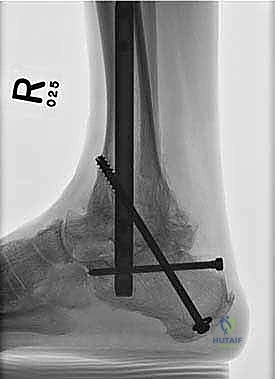

يتم هذا الدمج باستخدام مسمار نخاعي (Intramedullary Nail) طويل وقوي يُدخل من أسفل الكعب ليخترق العظام الثلاثة، ويتم تثبيته ببراغي قفلية لضمان أقصى درجات الثبات. الهدف من إلغاء الحركة في هذه المفاصل التالفة هو القضاء التام على الاحتكاك العظمي الذي يسبب الألم المبرح، مما يوفر للمريض قاعدة ثابتة وقوية للمشي.

4. إدخال المسمار النخاعي

يتم عمل شق صغير أسفل الكعب. يتم إدخال سلك توجيهي، يتبعه إدخال المسمار النخاعي القوي المصنوع من التيتانيوم. يخترق المسمار عظمة الكعب، ثم يمر عبر عظمة الكاحل، ليستقر أخيراً داخل القناة النخاعية لعظمة الساق.

5. التثبيت بالبراغي القفلية (Locking Screws)

لضمان عدم تحرك المسمار أو دوران العظام حوله، يتم تثبيت المسمار ببراغي عرضية تخترق العظام والمسمار معاً من الأعلى (في الساق) ومن الأسفل (في الكعب والكاحل). يتم استخدام جهاز التصوير الإشعاعي (C-arm) داخل غرفة العمليات للتأكد من الموضع المثالي لكل مسمار.